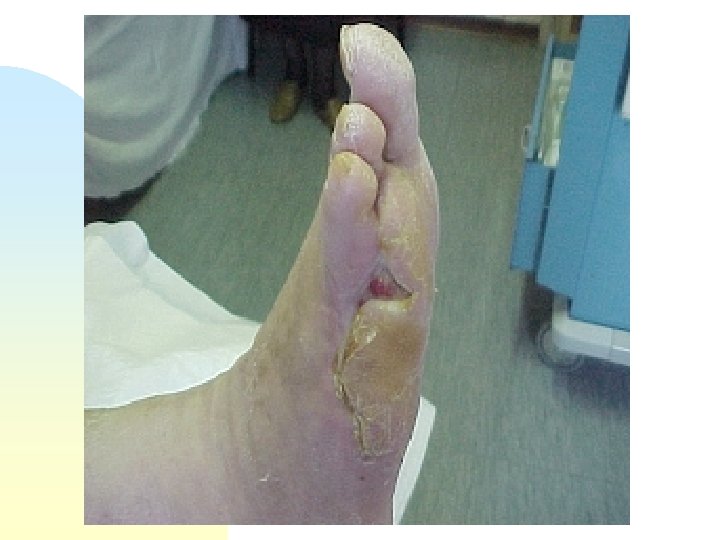

Maschio di anni 58 (P. E. ) con ulcera diabetica al piede di destra. Amputazione del IV e V dito del piede omolaterale.